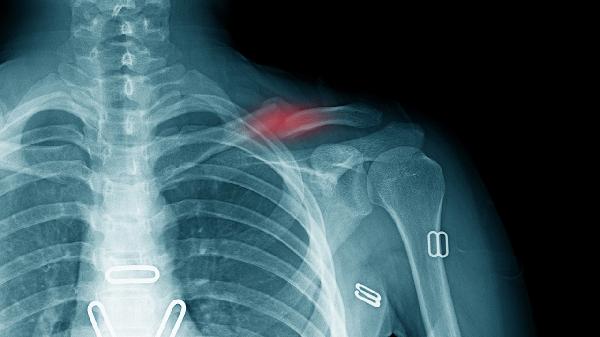

胸椎骨折一个月后能否下床需根据骨折严重程度和恢复情况决定。若骨折稳定且无神经损伤,经医生评估后可尝试逐步下床活动;若存在不稳定骨折或神经压迫症状,则需继续卧床休养。

若为不稳定性骨折或伴有脊髓损伤,一个月内禁止负重活动。这类骨折多由高处坠落、车祸等高能量损伤导致,常合并椎体爆裂、椎弓根断裂或椎管占位。过早下床可能导致骨折移位加重,甚至造成永久性神经损伤。患者需严格卧床6-8周,通过轴向翻身预防压疮,定期复查X线或CT观察骨痂形成情况。待影像学显示骨折线模糊、脊柱序列稳定后,方可在康复师指导下开始渐进式负重训练。